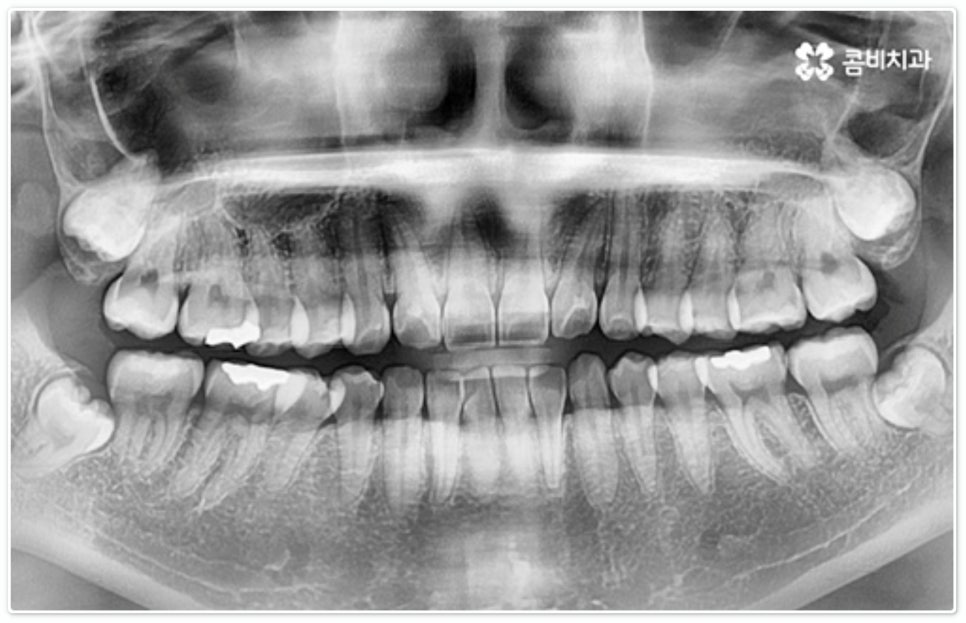

개개인의 치아와 잇몸 상황, 치열과 골격 상태, 교합 등을 자세하게 검진해 본 후에 부정 교합의 문제가 크지 않고 발치가 필요하지 않아 비교적 적은 힘으로도 치아 이동이 가능한 경우에 부분 교정 을 고려해 볼 수 있는 거예요. 즉 어금니 교합이 정상이고 턱관절 문제가 크게 관련되어 있지 않으면서 앞니의 각도만 뻐드러진 경우나 앞니 사이가 살짝 벌어진 경우와 같이 원인이 앞니에만 국한된 경우에 앞니부분교정 치료를 진행할 수 있으므로 정밀 검진과 충분한 상담이 선행될 필요가 있어요.

그렇지 않고 전후방 각도 조절 또는 단순 횡적인 움직임으로 치열 개선이 가능한 케이스는 부분 교정을 진행하는데, 사진에서 보시는 사례가 바로 그런 경우에 속하고 있습니다. 앞니 6개에만 브라켓을 부착하였는데 보시다시피 치아 색상과 유사한 세라믹 재질의 장치를 이용하여 심미성 또한 높여 주었음을 알 수 있어요.